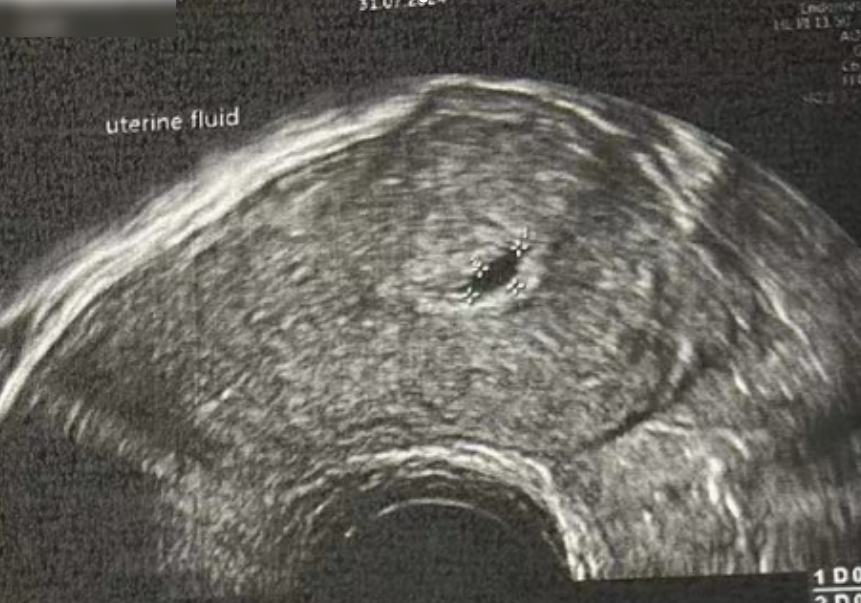

子宫内膜厚度:4.6 毫米,子宫有瘢痕大小 0.76*0.19 厘米

子宫内膜厚度:9.3-10 毫米

- 有粘液滞留在腔内,从峡部瘢痕延伸至子宫底

- 双卵巢无囊肿

- 计划在胚胎移植前重复超声检查以冲洗峡部瘢痕

子宫内膜厚度:8.9 毫米

在进行3毫升的子宫峡部切口冲洗后,经过经腹超声检查显示子宫内膜呈三线状,且子宫腔内未见液体。

• Pre-Irrigation灌洗前:

• Pre-Irrigation灌洗后: